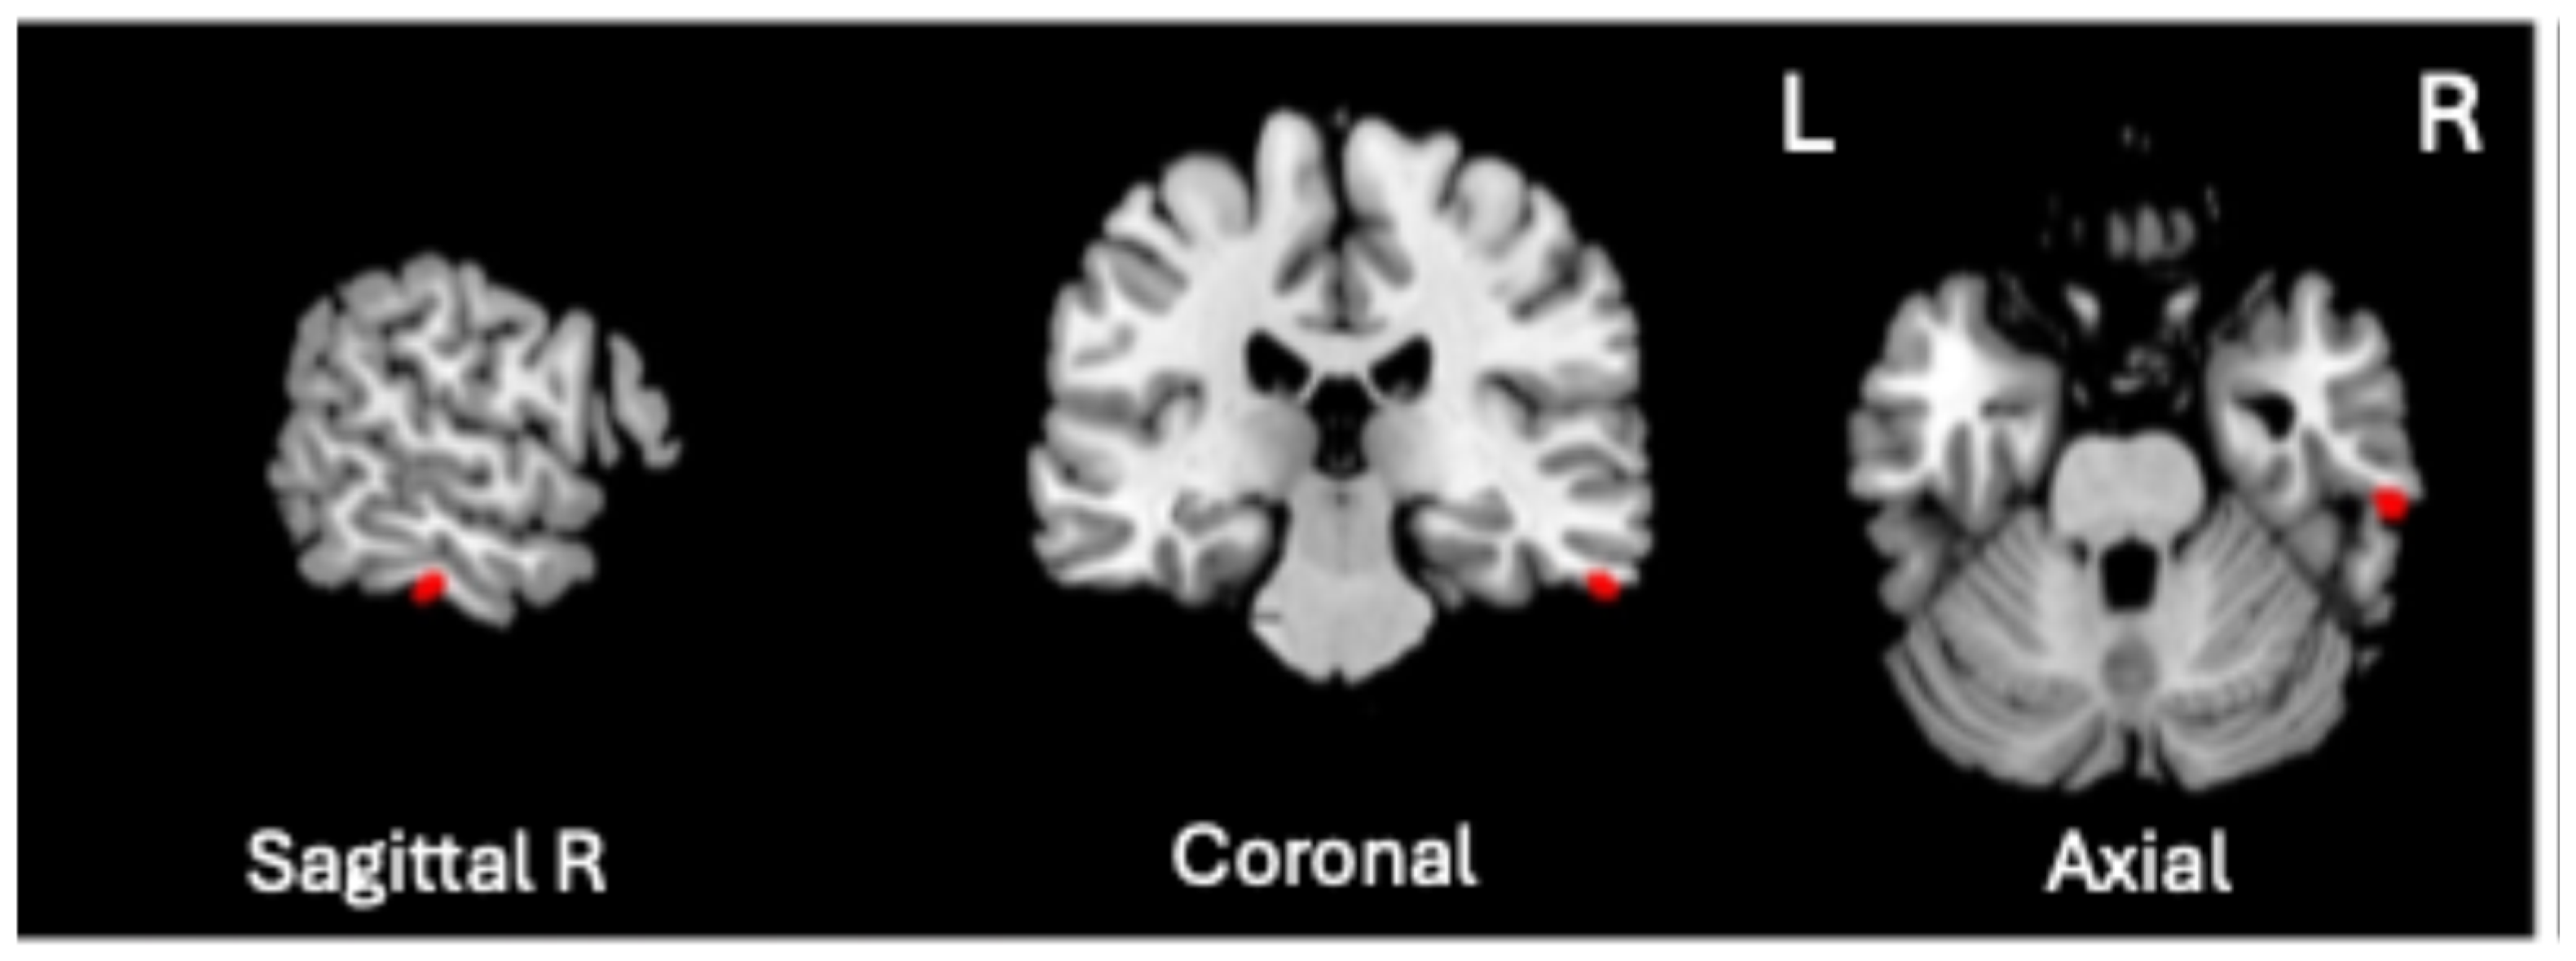

A significant positive association was found between VBM-GMV and Generalized Psychopathology scores only (t = 4.72, p = 0.0000057, q < 0.01, volume size = 82 mm3; Cohen’s d = 1.112). As shown in Figure 2, the greater the severity of Generalized Psychopathology, the greater the GMV in the right inferior temporal gyrus (ITG), corresponding to Brodmann Area (BA) 20 (MNI coordinates 61, −26, −28).

Figure 2.

Significant positive association between the VBM-GMV in the right inferior temporal gyrus (ITG) and the severity of Generalized Psychopathology PANSS subscale in SZ patients (q < 0.01).